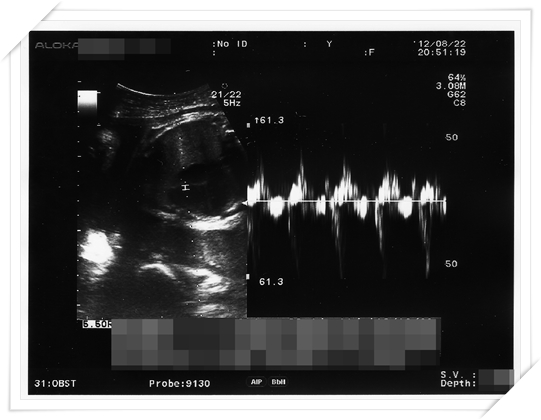

Mr.E 也忍不住問醫生說 小鴨的頭現在在哪阿?

醫生維持他一貫幽默的回答方式 說“在下面阿! 我沒說就表示胎位沒有不正!”

哈哈哈 好啦 沒消息就是好消息 我猜得果然沒錯 小鴨自己把頭轉下去了

而為什麼我之前就猜對了呢

因為我那之前一兩個星期 就開始覺得 是有人一直故意在踢我的胃嗎?!?!!

害我沒孕吐的人 三更半夜明明肚子都空了還會反胃打嗝是怎樣!!